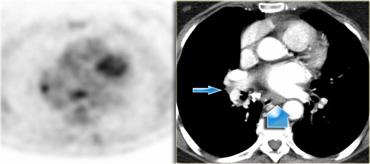

8. Hạch cạnh thực quản

Các hạch này nằm bên dưới các hạch dưới carina và trải dài xuống đến cơ hoành.

Bên trái là hình ảnh dưới mức carina.

Bên phải thực quản là một hạch nhóm 8.

Bên trái là hình ảnh PET cho thấy sự hấp thu FDG tại hạch nhóm 8.

Trên hình CT tương ứng, hạch không to (mũi tên xanh).

Khả năng đây là hạch di căn là cực kỳ cao, vì độ đặc hiệu của PET đối với các hạch không to cao hơn so với các hạch đã to.